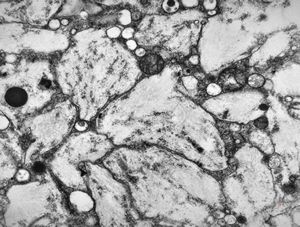

Whipple disease